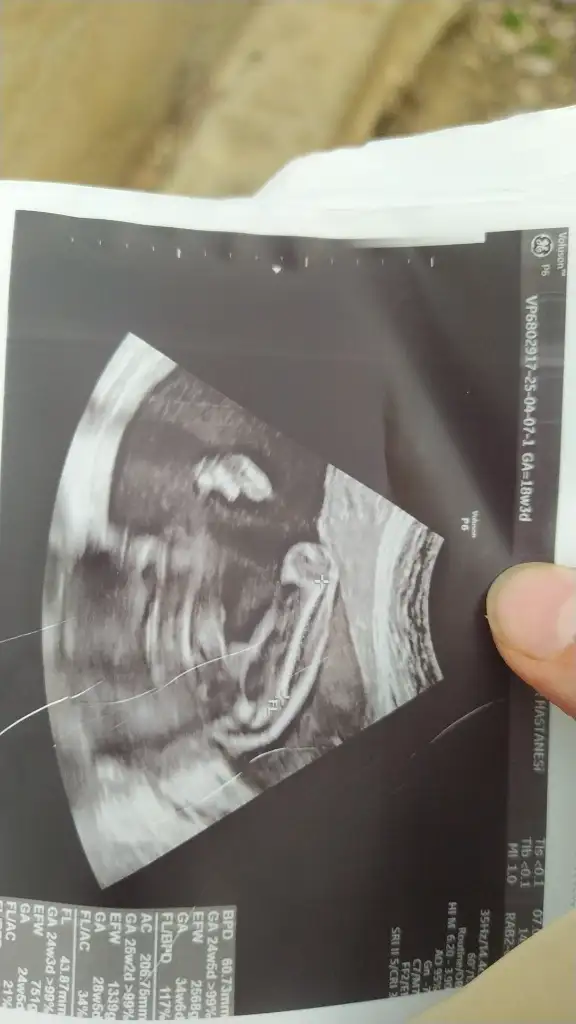

Arkadaşlar lütfen benimkisinde bakarmısınız 12. Haftada erkeğe benziyor dendi bu 12. Haftalık ultrason 16 haftada kız dendi sizce nedir